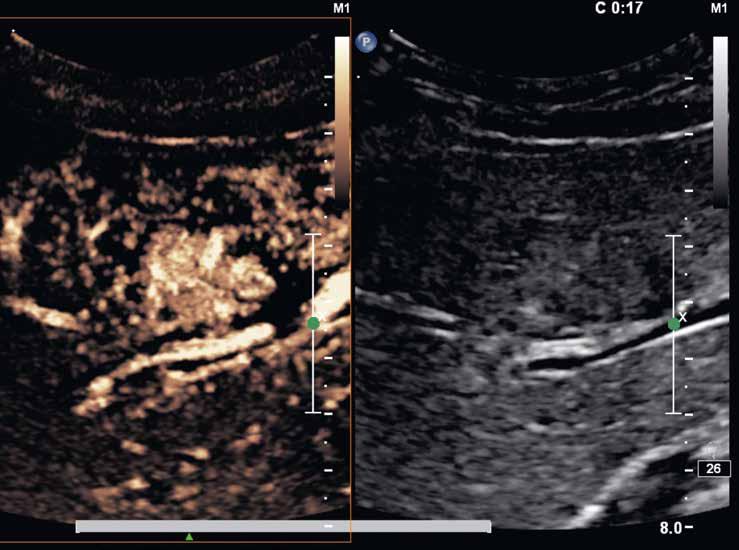

Na CEUS je v arteriální fázi patrný v levé polovině obrázku typický centrifugální charakter sycení ložiska, které je vidět v pravé polovině obrázku v B -módu (jako hypoechogenní) (6–8). Na CT (9) i MR (10) se ložisko (z obr. 4, 5) sytí homogenně, vyjma centrální vazivové jizvy, která zůstává hypodenzní.

V portovenózní fázi je ložisko izodenzní na CT (11), respektive izointenzní na MR (12).

V pozdní fázi je charakter ložiska stejný a nedochází k jeho vymývání ani na CT (13), ani na MR (14).

V centrální části ložiska je patrná vazivová jizva, která zůstává v arteriální fázi hypodenzní (9) a sytí se v pozdní fázi, kde je oproti zbytku ložiska hyperdenzní (13). Na MR je v T1-váženém obraze vazivová jizva hypointenzní (15), v T2-váženém obraze hyperintenzní (16).

Na MR ve fázi ekvilibria je v levém laloku patrné vcelku izointenzní ložisko s naznačeným hyperintenzním periferním prstenčitým lemem (17).

Po 20 minutách při použití hepatospecifické kontrastní látky je ložisko izointenzní až lehce hyperintenzní (18).